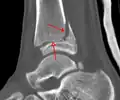

A triplane fracture of the ankle as seen on plain X-ray -

A triplane fracture of the ankle as seen on CT -

A triplane fracture of the ankle as seen on CT

- Triplane fractures are a special type of fracture that involves the immature skeleton. It has a coronal plane in the metaphysis, an axial plane in the physis, and a sagittal plane in the epiphysis.[15]